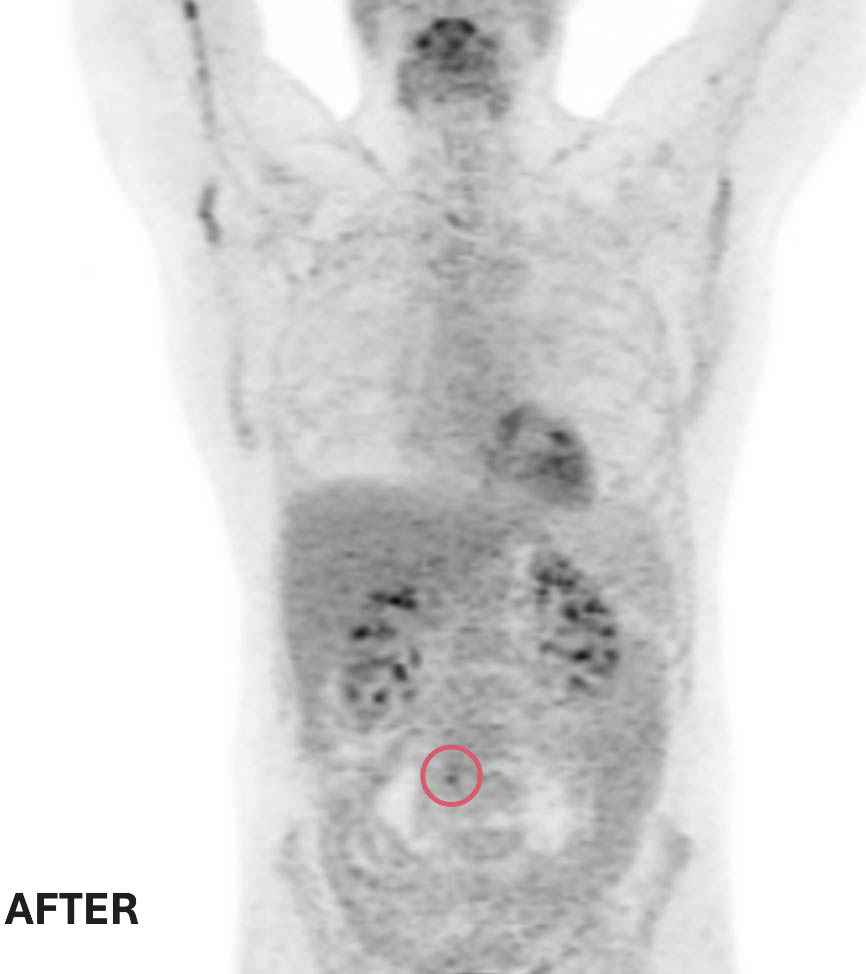

La réponse de Ted au traitement est extraordinaire. Les examens de tomodensitométrie de suivi montrent que les deux petites masses ont complètement disparu et que la grosse tumeur abdominale a rétréci jusqu’à devenir plus petite qu’un petit pois. Compte tenu de la nature agressive du lymphome à double impact, l’équipe de soins de Ted recommande une courte série de séances de radiothérapie pour éliminer toute cellule cancéreuse restante, une mesure préventive visant à réduire le risque de récidive.

Clichés d’imagerie médicale avant et après ses traitements : deux des trois tumeurs de Ted ont complétement disparu. La troisième est maintenant de la taille d’un petit pois – Ted répond très bien au traitement suivi à L’Hôpital d’Ottawa.